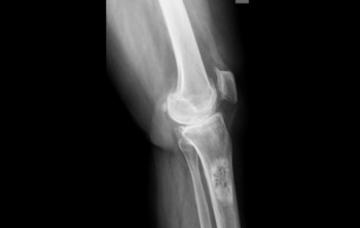

Tipos de cáncer óseo

Te explicamos en qué consisten los tipos de cáncer óseo más comunes, como el osteosarcoma, el condrosarcoma, el sarcoma de Ewing y la metástasis.